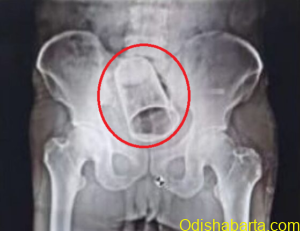

Odishabarta Berhampur: In a bizarre incident, a man from Odisha’s Ganjam district carried a steel glass inside his body with...